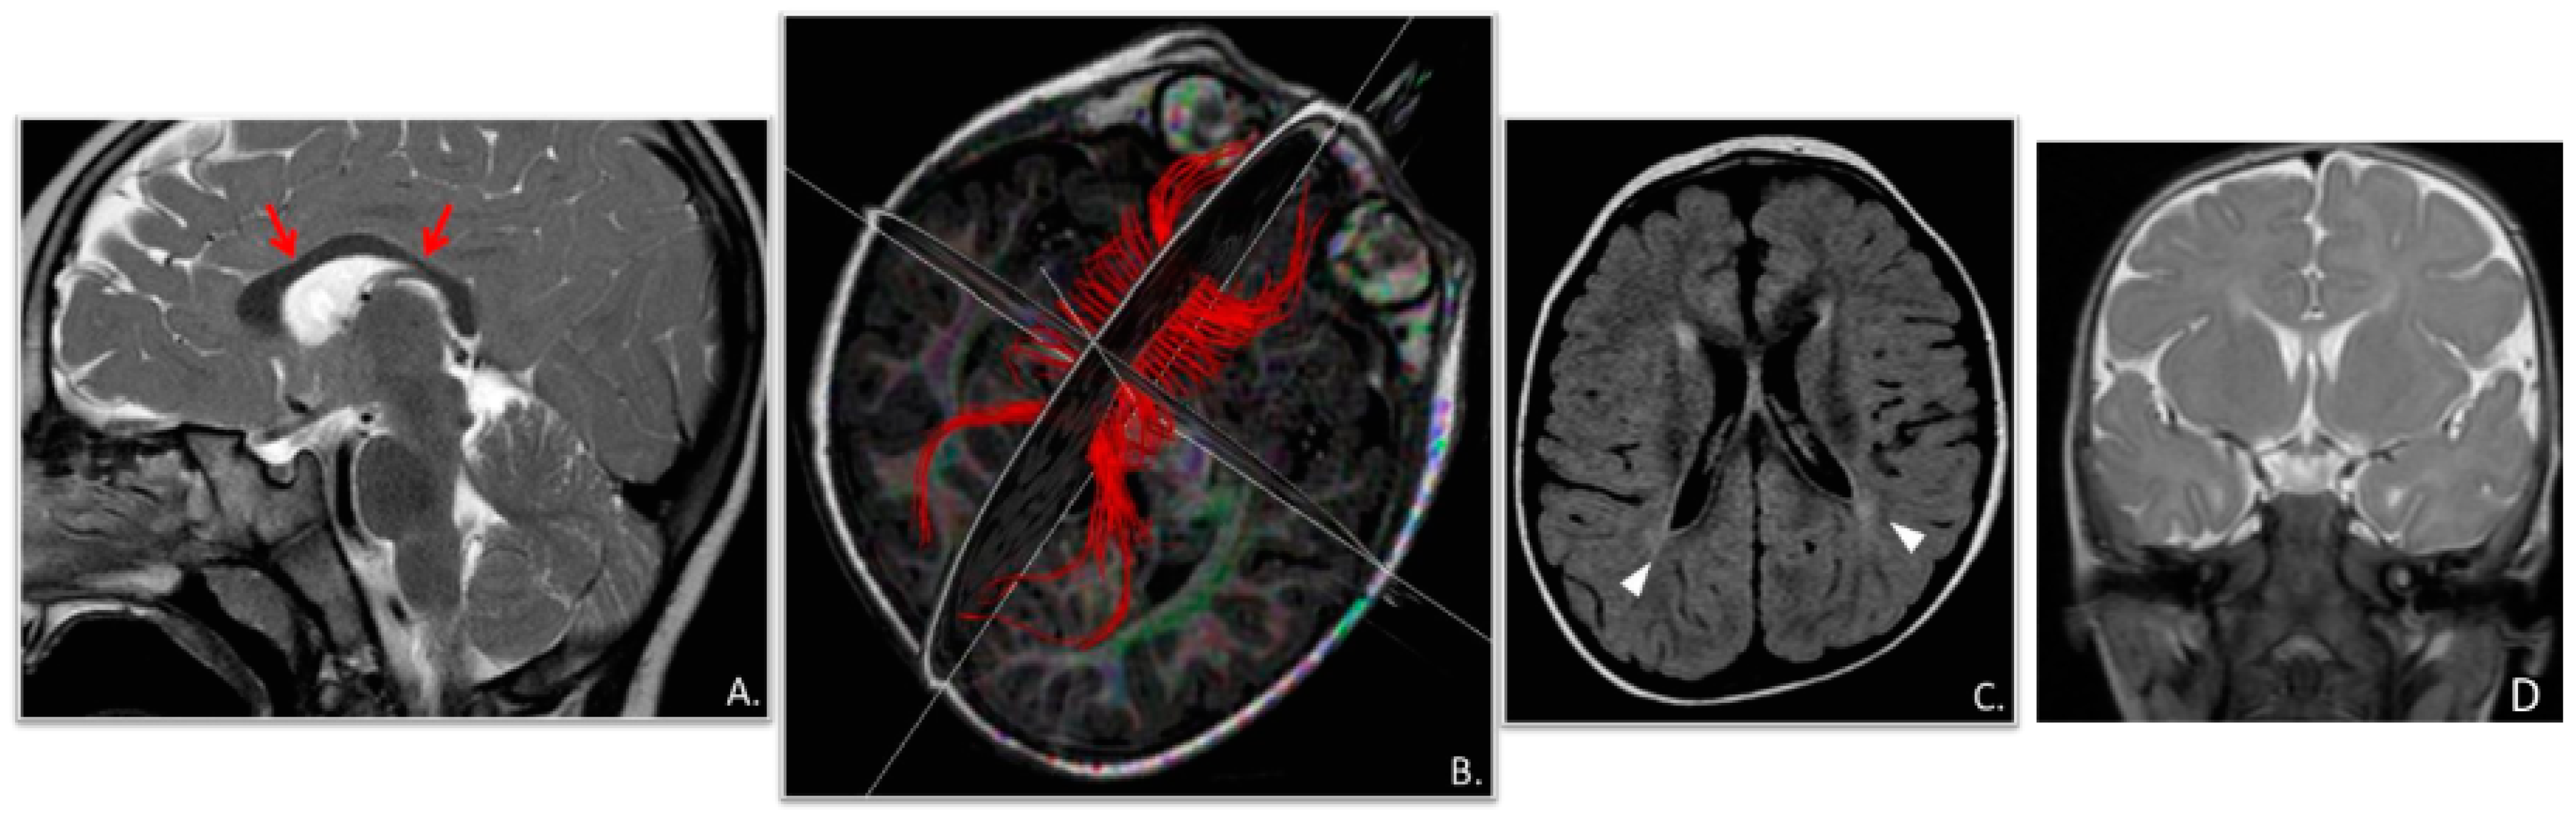

| Cranial MRI abnormalities | + | + | − | + | − | − | − | − |